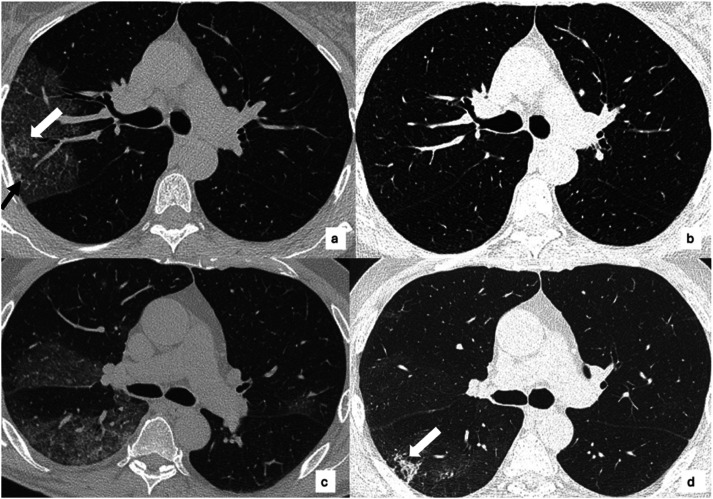

Background: COVID-19 patients may have residual pulmonary alterations after the acute disease, with fibrotic-like alterations. Since metalloproteinases (MMP) and their regulators may be involved in inflammation and abnormal repair processing, we aimed to investigate the correlations between MMP-9, a tissue inhibitor of metalloproteinases (TIMP-1) and chest CT abnormalities in acute phase and mid-term follow-up.

Methods: COVID-19 patients with plasma analyses and CT scans performed at acute onset and 3 months after discharge (T post) were evaluated. MMP-9, TIMP-1, and MMP-9/TIMP-1 ratio were analyzed. CT extents of COVID-19 pneumonia and fibrotic-like alterations were visually scored (score range 0-25). Spearman rank correlation analysis (p-value <.05) was computed between acute and mid-term plasma analyses and CT scores.

Results: 39 patients were enrolled. At hospital admission, MMP-9, TIMP-1, and MMP-9/TIMP-1 had a median of 240.5 ng/mL, 258.8 ng/mL, and 0.9. The median CT global and fibrotic-like scores were 9 and 6. At T post, MMP-9 and TIMP-1 were not statistically different (p-value <.05). There was a reduction of CT global score (p-value = .00007). A significant correlation was found between MMP-9 and CT global score at hospital admission (ρ = 0.456, p-value = .003) and between MMP-9/TIMP-1 ratio and CT global score at hospital admission (ρ = 0.406, p-value = .009). No other significant correlations were found between plasma enzymes and CT alterations, both in acute and mid-term follow-up.

Conclusion: MMP-9 plasma levels and MMP-9/TIMP-1 ratio correlate with lung involvement during the acute phase. None of the levels of MMP-9, TIMP-1, and MMP-9/TIMP-1 ratio may be adopted as predictors of residual pulmonary alterations in mid-term follow-up.